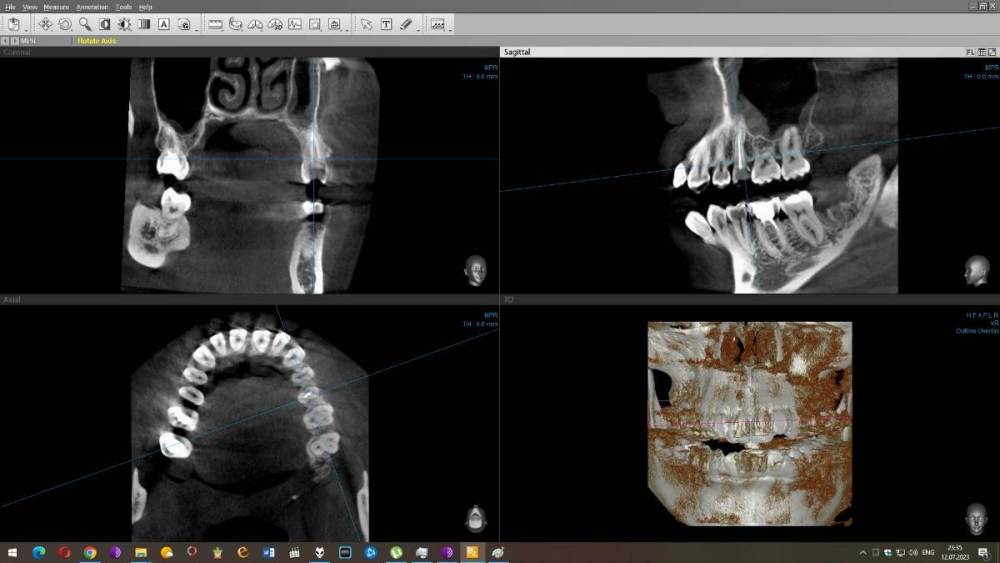

Mariaduya Опубликовано 5 июля, 2023 Поделиться Опубликовано 5 июля, 2023 (изменено) Здравствуйте. У меня сложная ситуация, боли в челюсти практически 1.5 года. Врачи не видят проблем, уже не знаю куда обратиться. Хронология. 1. В ноябре 2021 начал слегка болеть 1.6 зуб. В стоматологии мне его сразу начали депульпировать, без снимка. В ходе лечения не болел, как запломбировали каналы, постепенно появилась ноющая, постоянная боль. Я обратилась снова, сказали, что на зубе есть хроническое воспаление и ввели антибиотик туда при помощи электрофареза. Среагировал 2.5 зуб с другой стороны, и тоже начал постоянно болеть, он был депульпирован давно, но в нем развился большой кариес. 2. Мне начали их перелечивать. 1.6. не получилось пройти канал, залили резодентом, 2.5 просто переличили. 3. Боль все ещё осталась, уже в двух зубах. Врачи ничего не знают, отправили к неврологу, ЛОРУ и т.д. 4. Обошла неврологов, лоров, делала мрт, кт с контрастом головы, пазух носа, все ок. Невролог выписывает финлепсин, не помог. 5. Делала в частной клинике кт зубов, без описания, ещё не знала, что оно нужно, врач посмотрела и сказала, что видит небольшое, хроническое воспаление на 1.6 зубе и все, а так она не знает. 6. И так 1.5 года никто не знает, что со мной. Боль 1.6 и 2.5 зубы, начинают и нижние зубы болеть, уже и ухо болит. После орви болит все очень сильно, что хочется уже не просыпаться. Удалять их говорят не показаний, вдруг боль останется. Снимки в хронологии выкладываю. Есть ли на них воспаление 1.6 зуба, 2.5 зубов, есть ли них кисты свищи и все что угодно, что аномально и может вызывать боль. Может что-то с надкостницой, или суставами. Все что у меня есть - интернет, так как живу я очень далеко от нормального города и доступна только городская поликлиника, где врачи говорят, что это неврология, а невролог говорит наоборот. Сами зубы болят странно, по очереди. Если болит неделю 1.6 зуб, то 2.5 не болит и так наоборот. Вместе они не болят. Ещё странное то, что они практически симметричны друг другу по расположению. Изменено 5 июля, 2023 пользователем Mariaduya Ссылка на комментарий

wladdX Опубликовано 12 июля, 2023 Поделиться Опубликовано 12 июля, 2023 Исследование от 27.12.2021. Лучше бы поновее Ссылка на комментарий

Carioznik Опубликовано 13 июля, 2023 Поделиться Опубликовано 13 июля, 2023 по этому старому КТ: на 16 - есть пропущенный канал, от этого, на одном из корней - есть небольшой воспалительный процесс (на тот момент). "Само не заживет", будет только расти, может, на сегодняшний момент - уже стал большой). Но жалобы в таких случаях обычно другие. Делайте новое КТ (по старому только гадать...) и снова, очный осмотр стоматолога, явно понадобится. 1 Ссылка на комментарий